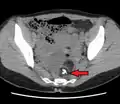

Dermoid cyst in vaginal ultrasonography

A complex cyst due to a dermoid as seen on CT. Arrow points to bone or teeth.